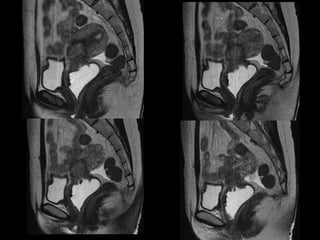

HISTORY

• 40 yo female 8.5 weeks pregant

• S/P D&C for pregnancy implanted at site of

c-section scar

• 6 weeks post D&C patient presents with

heavy persistent bleeding

• For Pelvic US

• HCG = 451 mIU/mL

• What are the findings?

• What is the differential diagnosis?

• What are your recommendations?

• What is the diagnosis?

• What is the treatment?